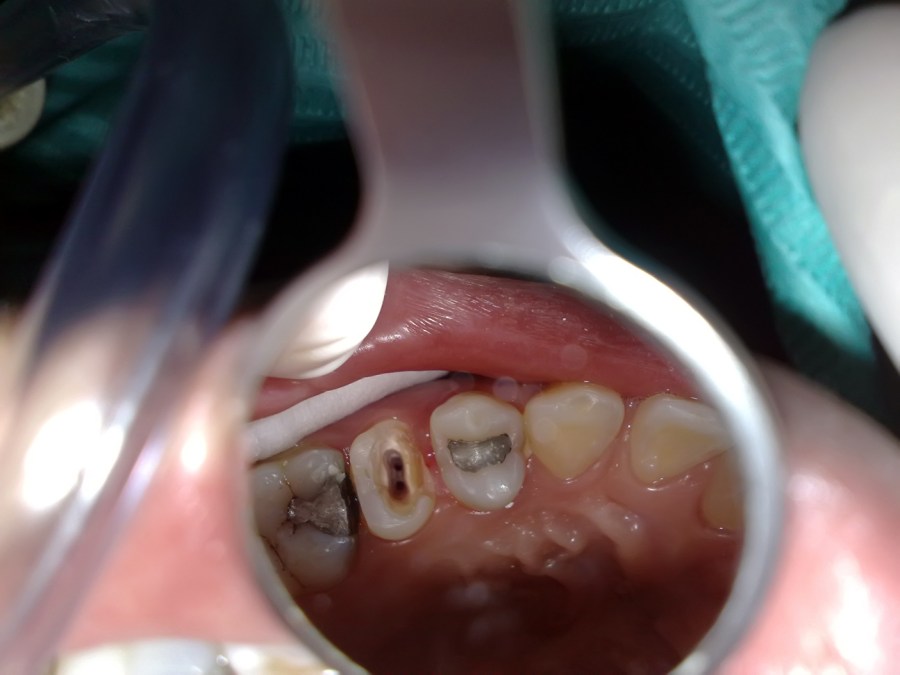

Endodontic treatment on upper left first molar with broken mesial and distal wall